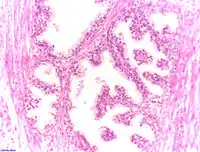

Adénocarcinome prostatique

Adénocarcinome ; tissus indifférenciés

Invasion périneurale par un adénocarcinome prostatique. HE, x400

Anatomopathologie

Le cancer entreprend la portion périphérique de la glande, au contraire de l'hypertrophie prostatique bénigne qui intéresse la zone centrale, périurétrale.

Des études ont montré que des fibres nerveuses (issues de prolongements d'axones de neurones préexistants dans le système nerveux périphérique) peuvent infiltrer les adénocarcinomes de la prostate, contribuant aux phases précoces du développement tumoral et à sa progression[49]. Par ailleurs, le système parasympathique cholinergique régule l’invasion tumorale et l'émission de métastases, en activant le récepteur muscarinique de type 1 (Chrm1) du microrenvironnement tumoral[50]. En 2019, le même laboratoire découvre que des neurones peuvent être créés au sein même du microenvironnement tumoral[51]. Ils y sont produits par des cellules neurales souches provenant du cerveau et acheminées par la circulation sanguine. En effet, on trouve dans les tumeurs, des cellules exprimant une protéine, la doublecortine (DCX), généralement exprimée par les cellules progénitrices neuronales, lors du développement embryonnaire et, chez l’adulte, dans les deux zones du cerveau où les neurones se renouvèlent : le gyrus denté dans l’hippocampe et la zone sous-ventriculaire. Une corrélation entre sévérité du cancer et taux de cellules DCX+ est observée. Il a été mis en évidence chez la souris, que la présence de tumeur est associée à des anomalies de perméabilité de la barrière hématoencéphalique de la zone sous-ventriculaire, permettant la migration dans le sang de cellules DCX+ depuis cette zone sous-ventriculaire. Ces cellules se retrouvent dans la tumeur et les nodules métastatiques où « elles se différencient en neuroblastes puis en neurones adrénergiques producteurs d’adrénaline » ce qui pourrait favoriser la vascularisation et le développement des tumeurs[52].

La gravité de l'évolution est corrélée avec l'aspect microscopique (score de Gleason), le niveau de PSA et l'extension de la maladie[53].